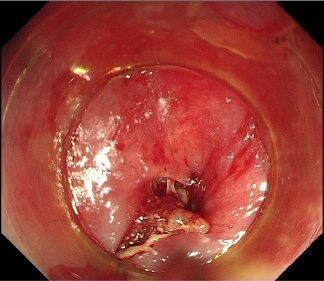

消化内科主治医师李浩然和微创中(第二手术区)心护士长刘骥为患者行内镜下食管内异物取出术。术中可见一枣核卡顿于食管入口处,周围黏膜充血水肿伴破溃。使用异物钳钳取枣核头端,拖入透明膜内与内镜共同退出。二次进镜,食管入口处黏膜可见血肿、破溃及少量渗血,并行内镜下空肠营养管置管术。

术中可见一枣核卡顿于食管入口处,周围黏膜充血水肿伴破溃

使用异物钳将枣核取出,食管入口处黏膜可见血肿、破溃及少量渗血。